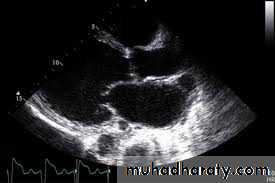

#ECHO : although ventricul not dilated ;the

1-atrium is dilated – Ventricul not dilated2-diastolic dysfunction- reduce ventricular volume

#CXR : may be normal

pleural effusion

JVP elevated and tender hepatomegaly ,Echo reveals normal size ventricles with biatrial dilatation